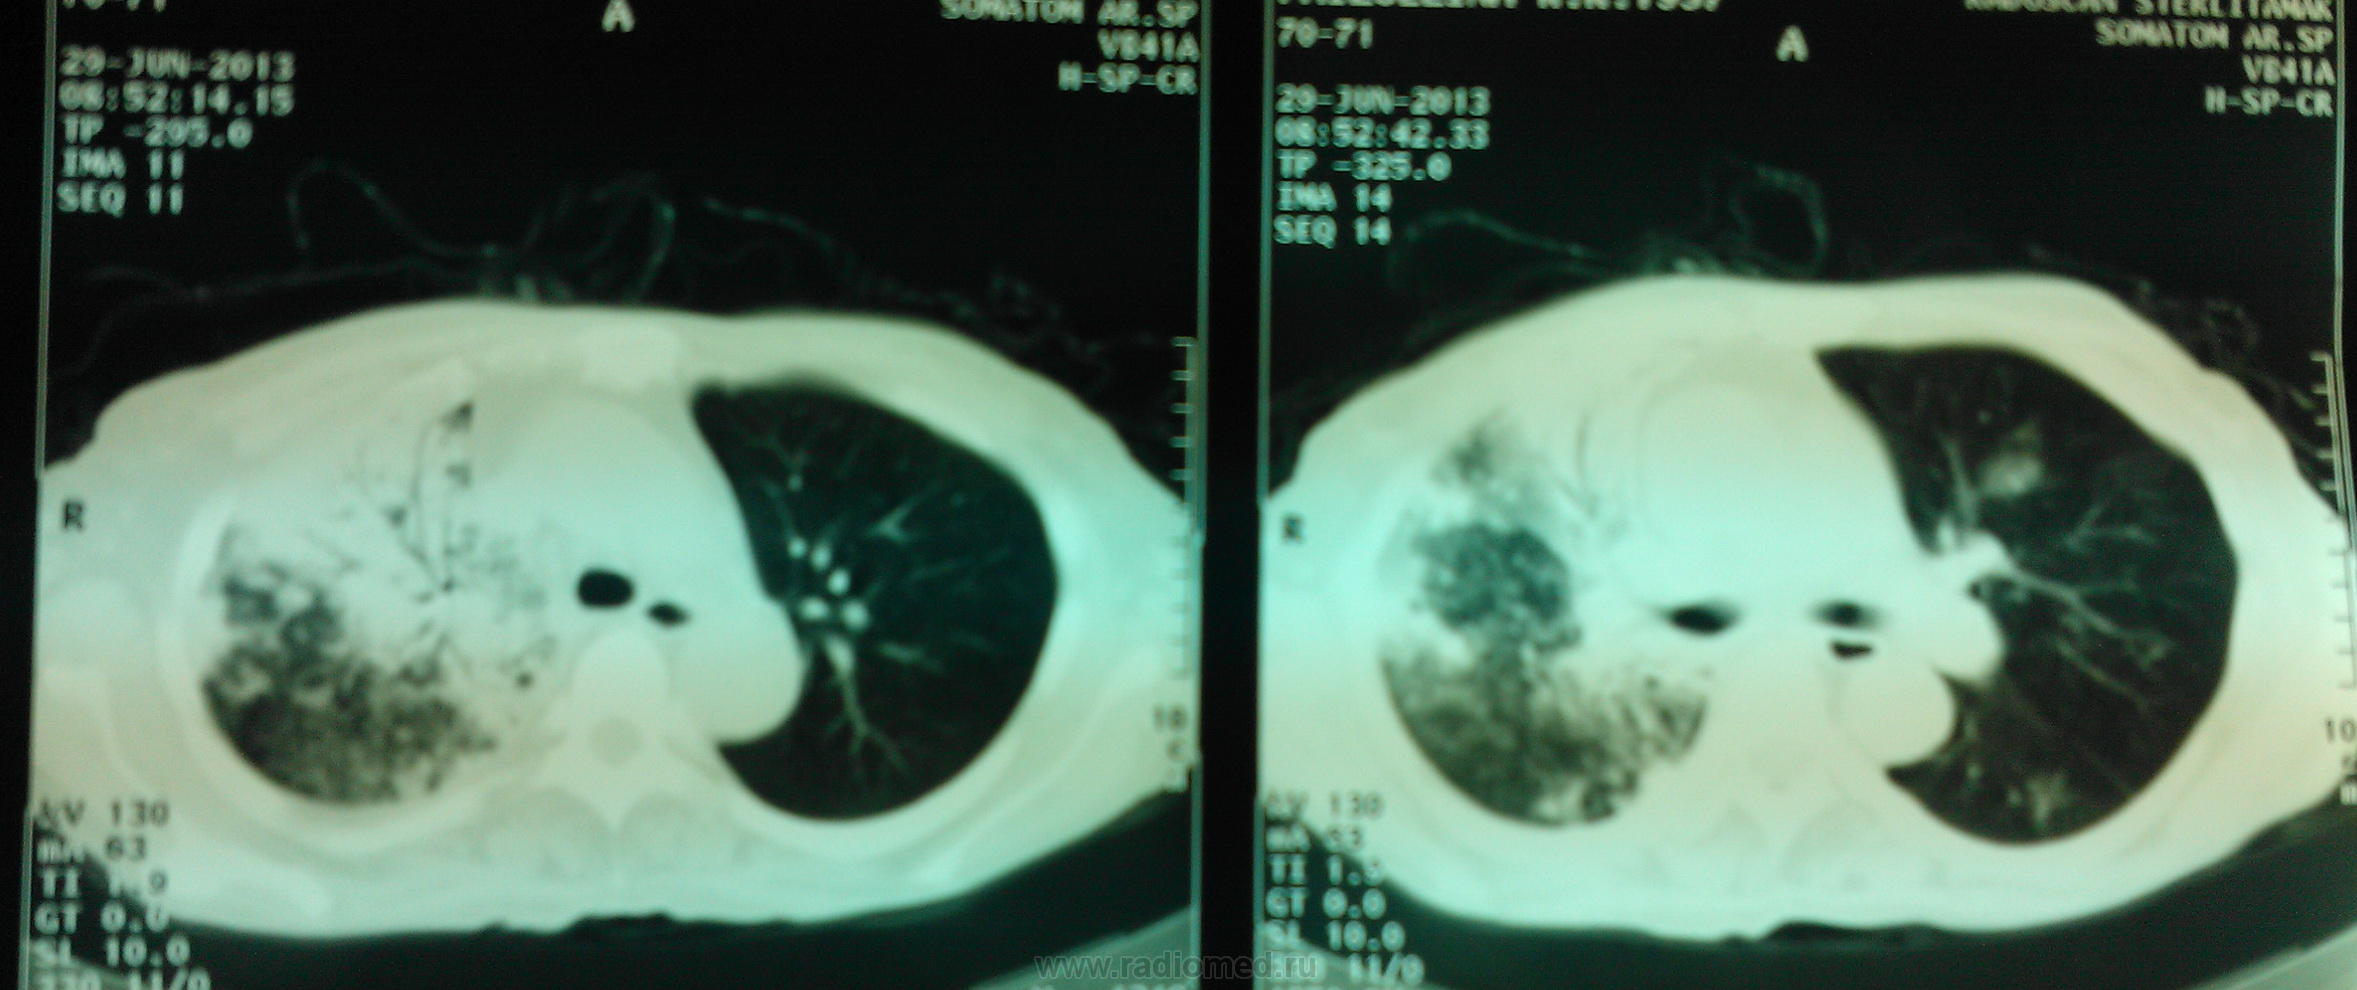

Женщина пенсионного возраста поступила в отделение сестринского ухода при терапии с диагнозом "Алкогольная интоксикация", жалоб особых нет, раннее не обследована, из анамнеза злоупотребление алкоголем. после проф. флюшки отправлена на консультацию к онкологу и фтизиатру. фтизиатр свое исключает и также отправляет к онкологу, онколог рекомендует КТ ОГК, на КТ врят ли поедет так как из глухой деревни, в анализах крови ничего особенного, хотеллось бы узнать мнения коллег по данному случаю.

еще немного из анамнеза: больной считает 7 дней, беспокоят боли в животе (в эпигастрии), 10 дней злоупотребляла алкоголем, в анализах лейкоциты 7,6 (палочки 12, сегменты 60, моноциты 3, лимфоциты 25), эритроциты 4,7 соэ 7 мм\ч, и т.д. б\х крови, ОАМ без изменений, гепатит отриц. по анализам везде норма. резко не худела, кашля нет, зацепиться не за что кроме рентгенограмм ОГК. и еще в теплице была обработка ядохимикатами, что натолкнуло меня на мысль уж не дольковый ли отек правого легкого? что скажете коллеги?

Случай достаточно непростой. Сразу обратил внимание на выраженую компенсаторную эмфизему левого легкого. Правое значит очень плохо функционирует. И причиной этого может быть и обширность поражения, и бронхообструкция, и то и другое вместе. Полости могут быть и при туберкулёзе, и при абсцедирующей прневмонии, и при раке с распадом. Абсцесс вроде бы не вписывается в лабораторные показатели, но у хронических алкоголиков может быть убитый иммунитет. Туберкулез, на мой взгляд, при такой обширности, должен был дать отсев и в другое легкое. Так что, из этих рассуждений больше склоняюсь к раку. В таком неоднозначном случае всеравно следует оставить диф. ряд: рак, тбц, абсцедирующая пневмония и уговорить пациента на КТ, бронхоскопию.

По-моему это типичная картина активного туберкулеза - инфильтраты со склонностью к слиянию, очаги с нечеткими контурами.. Средостение смещено вправо, что может указывать на фиброз в правом легком.. Спокойные анализы, неяркая клиника туда же - к туберкулезу. На каком основании фтизиатр так быстро сказал, что это не его?

провели кт: заключение по КТ ОГК - картина деструктивной полисегментарной пневмонии правого легкого, и сегментарной нижней доли левого, КТ ОБП - картина жировой дистрофии печени, киста левой почки. Сами снимки мне увидеть не удалось - родственники зачем то увезли в деревню, надеюсь привезут на днях и я хотя бы их сфотографирую для вас.